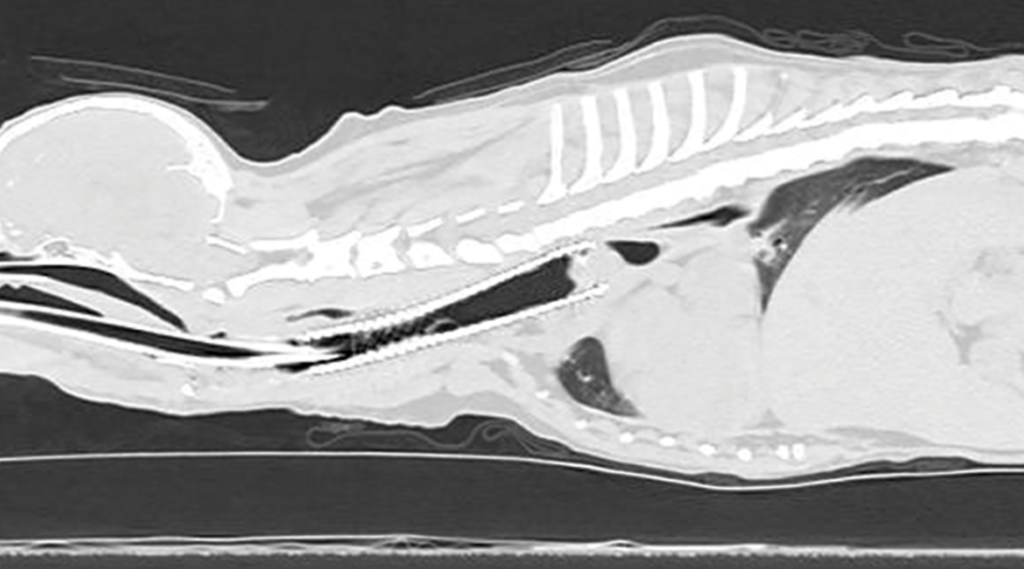

固定气管异常也越来越受到重视,称为气管畸形,其中气管永久固定在异常/阻塞位置(图 1)。与气管畸形相关的固定阻塞,通常靠近胸廓入口,会影响吸气和呼气;体征会随着兴奋或劳累而恶化。